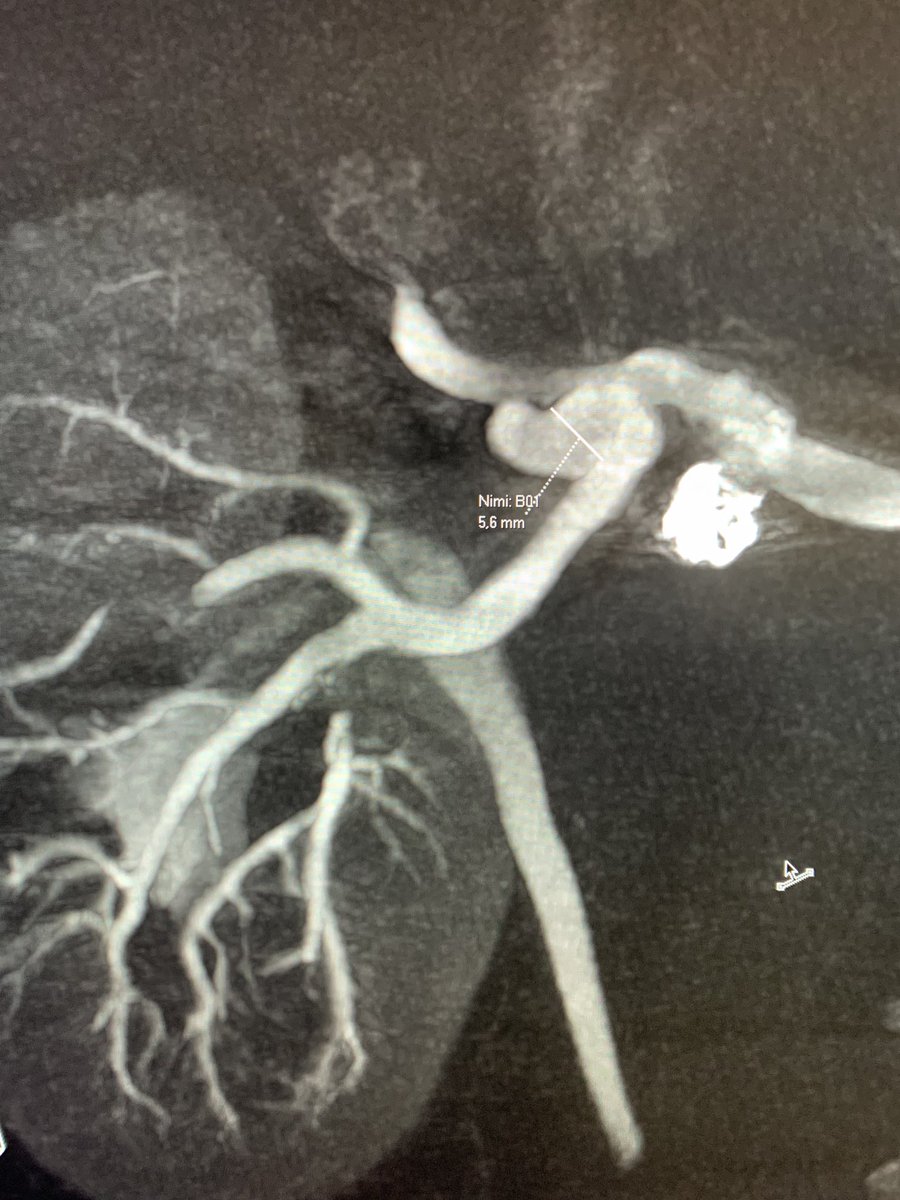

WEB can be used in various anatomical locations. We treated a wide-necked renal artery aneurysm with a WEB by ”corking” the neck. Immediate contrast stagnation!